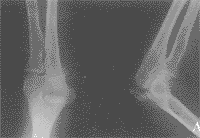

2.雙側X線攝片對比 肘關節化骨中心在融合前有可能與骨折混淆,可疑者應攝健側對比。

1.X線肘關節側位像因無移位骨折在正位像上往往表現不出。2.雙側X線攝片對比肘關節化骨中心在融合前有可能與骨折混淆,可疑者應攝健側對比。